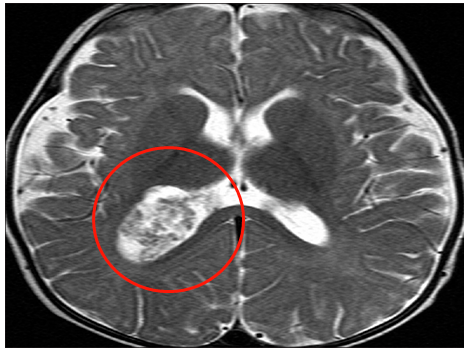

术前的检查显示,堂堂右侧脑室后角有一个大肿块,考虑脉络丛乳头状瘤病变,并有蒂连接,伴有中度脑积水。

鲁特卡教授通过右顶骨开颅手术和侧脑室切开后中央回后方的皮质切口。暴露血管高度丰富的肿瘤,夹紧蒂部并烧灼,然后顺利切除肿瘤。术后病理结果显示为脉络丛乳头状瘤。

经过鲁特卡教授的手术治疗,堂堂康复得十分顺利。两周后,堂堂的所有体征和症状均已缓解。CT扫描结果显示,脑积水减少,脉络丛正常。他平安出院,术后也无需任何辅助治疗。